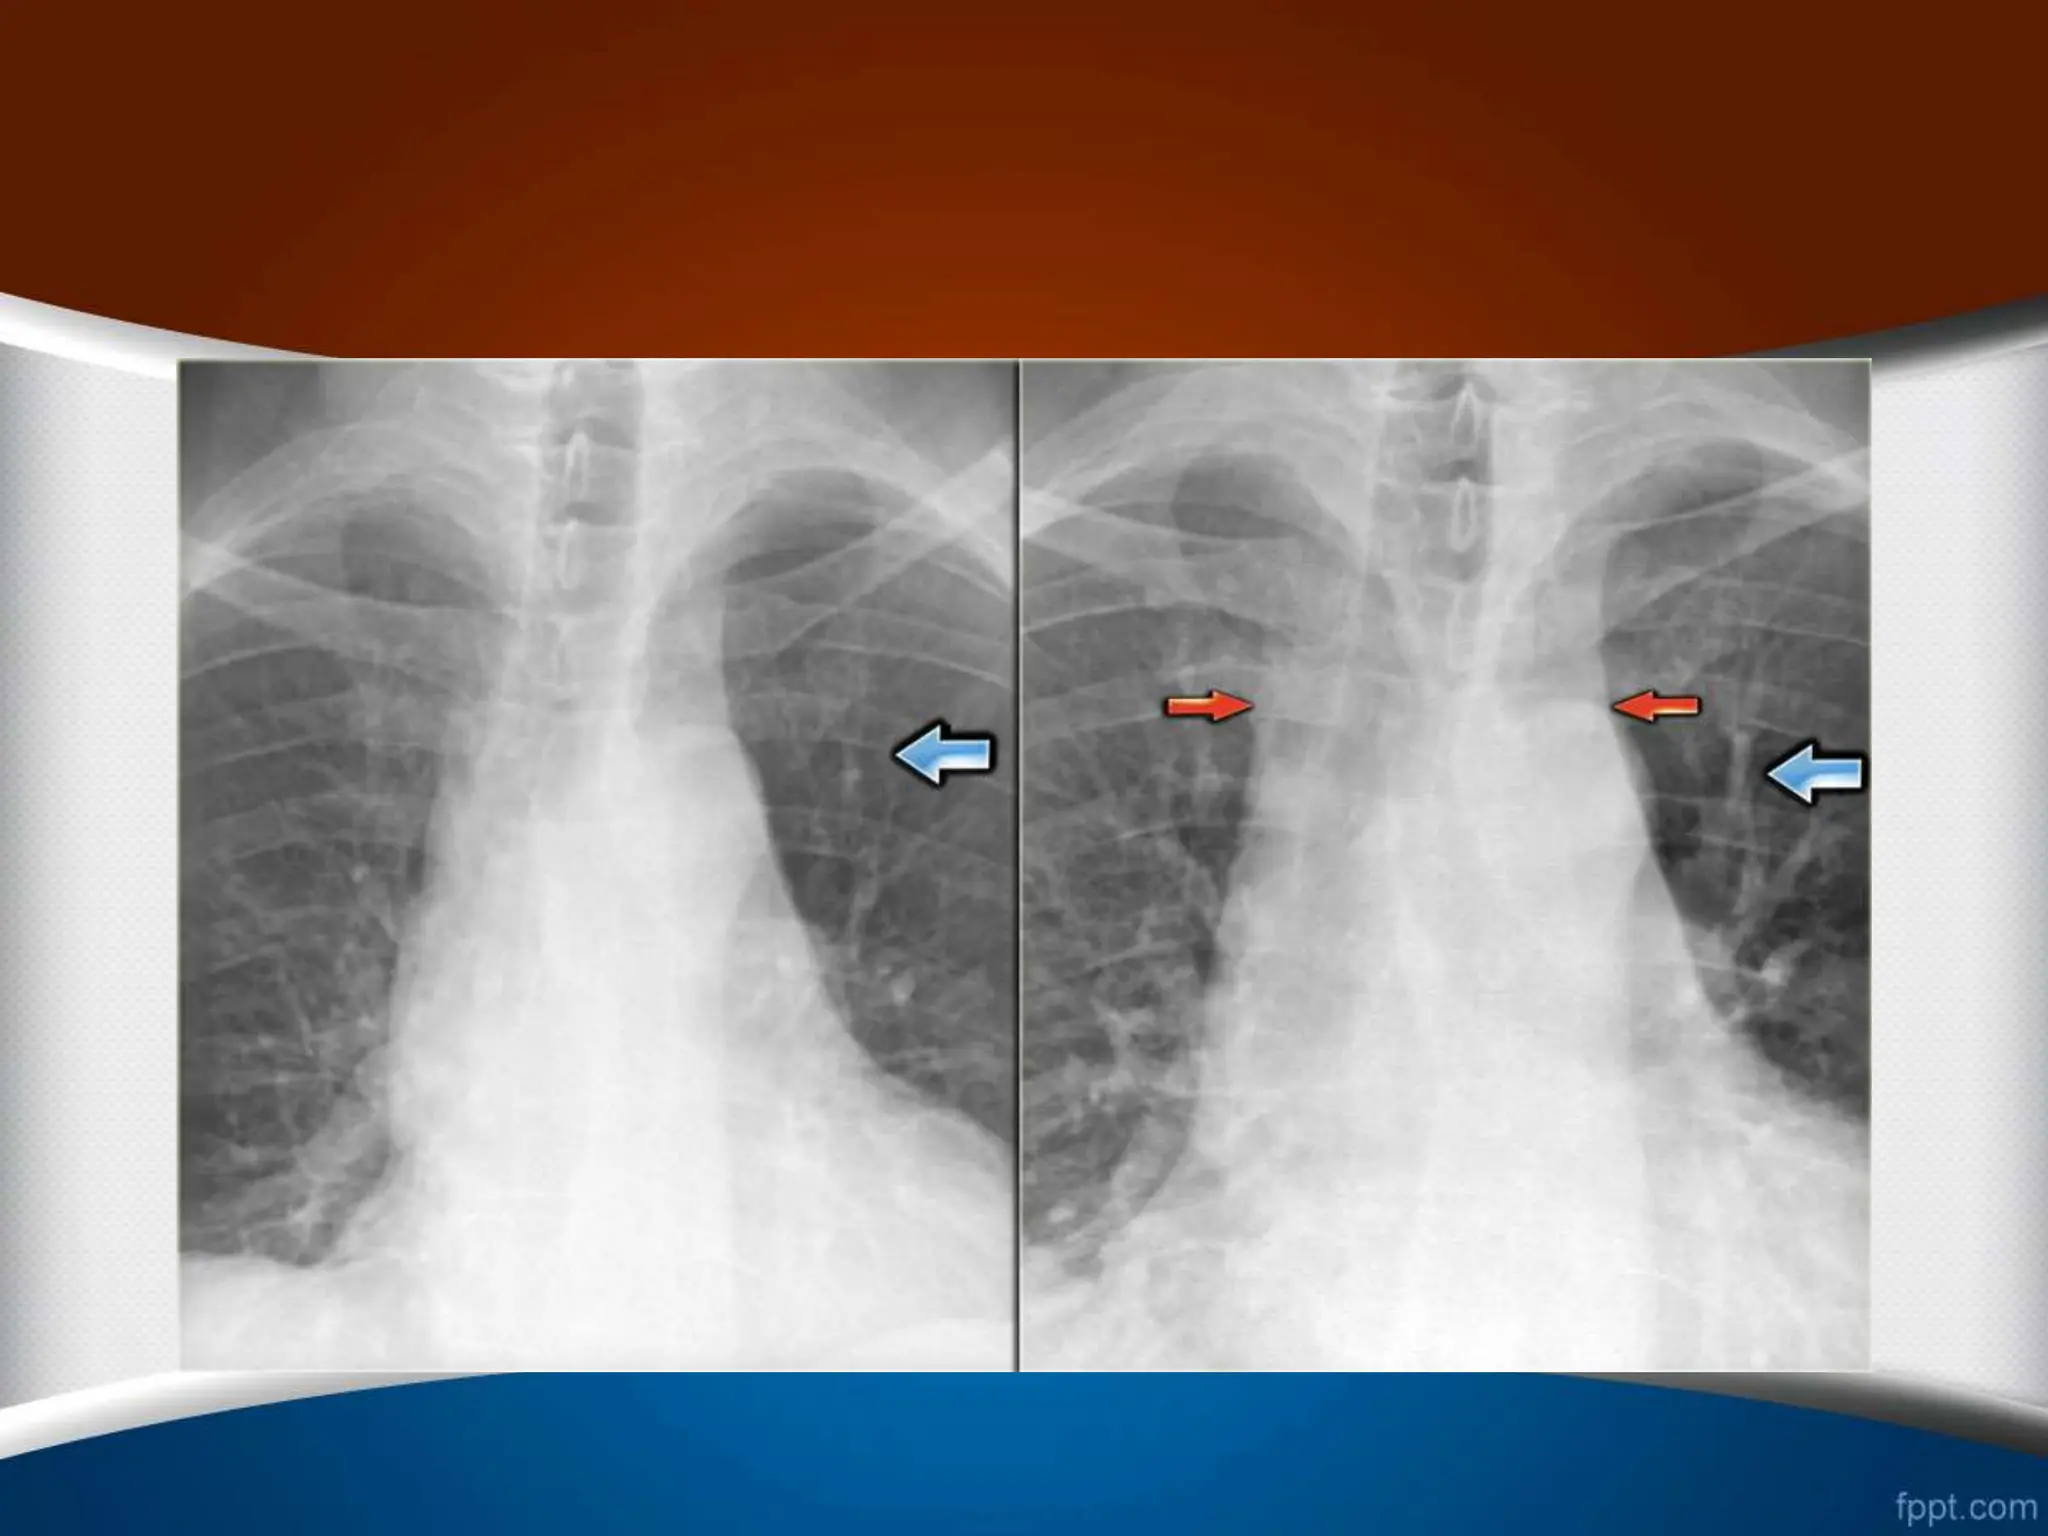

‫چپ‬ ‫به‬ ‫چرخش‬

.1

‫بزرگتر‬ ‫قلب‬

.2

‫خونتر‬ ‫کم‬ ‫چپ‬ ‫ریه‬ ‫فیلد‬

‫راست‬ ‫به‬ ‫چرخش‬

‫کوچکتر‬ ‫قلب‬

‫خونتر‬ ‫کم‬ ‫راست‬ ‫ریه‬ ‫فیلد‬

‫چپ‬ ‫به‬ ‫چرخش‬ ‫راست‬ ‫به‬ ‫چرخش‬